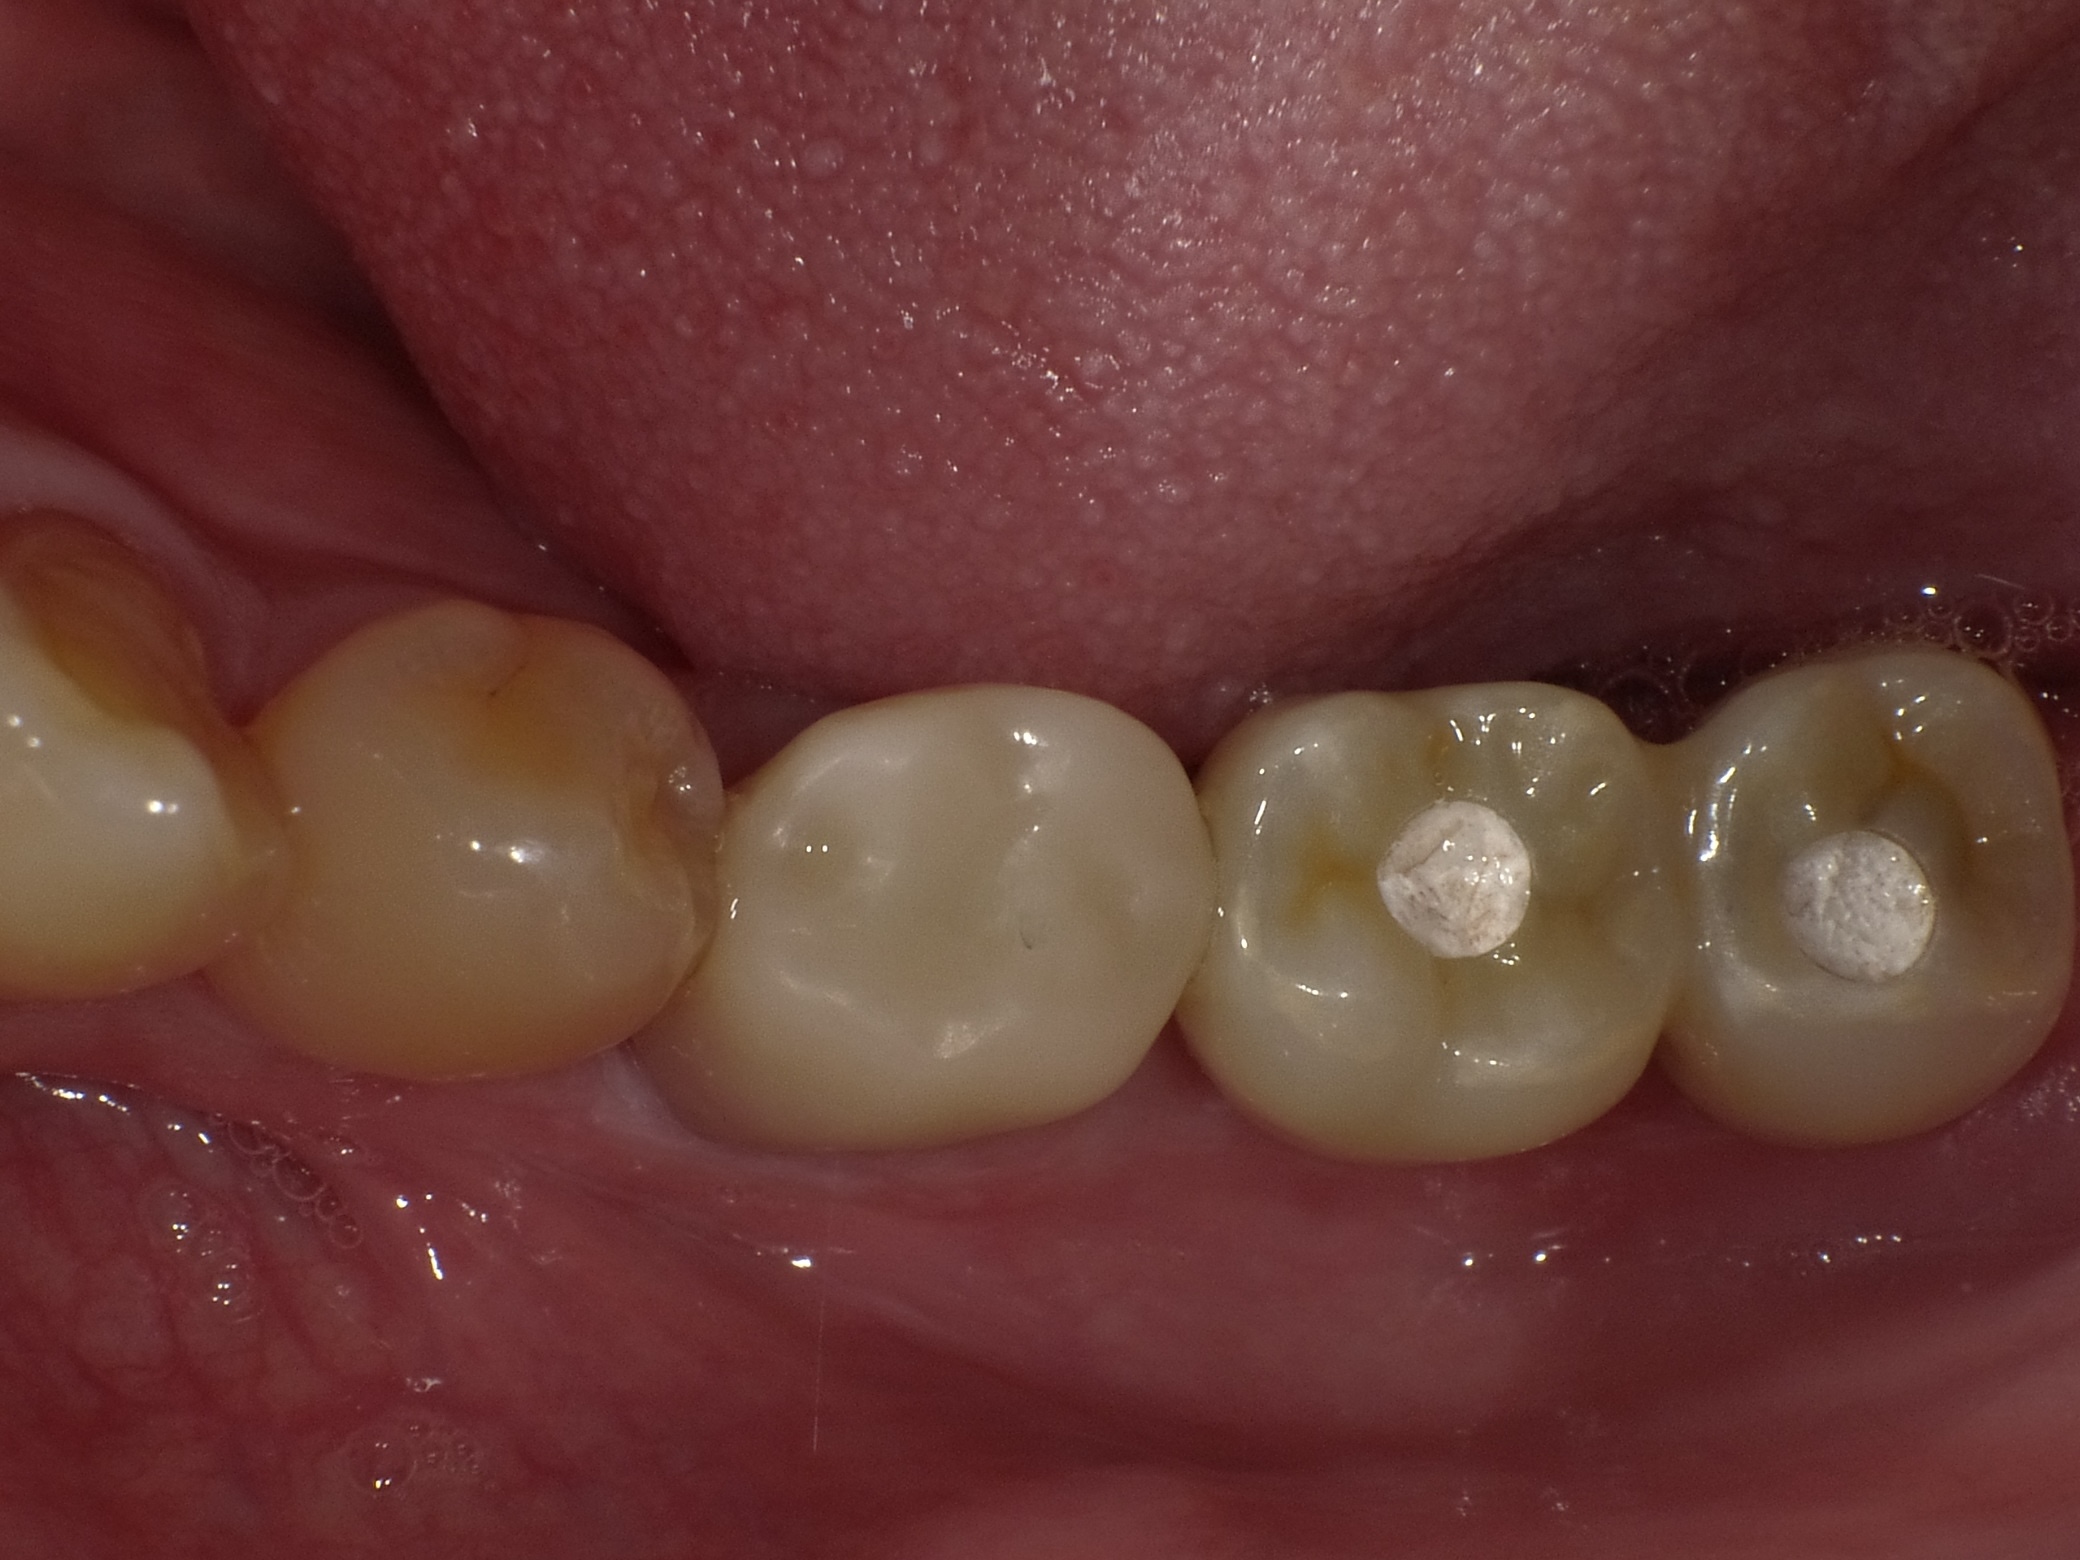

左下2本インプラント症例

主訴 奥歯でしっかり咬めるようにしたい(男性) 治療内容 左下の奥歯2本をインプラントにて治療しています。プラマRFインプラントを埋入。

手術後3ヶ月待ち、骨とインプラントが固まったことを確認し、二次手術後に型取りを行っています。当院では、ほとんどの症例でデジタルでの型取りを行っています。

インプラントを埋入した部位に型取り用のパーツをはめ、3Dスキャナーにて型取りをし、ジルコニアクラウンの被せ物を作製しています。完成後の咬合面は状態を確認後、埋めていきます。

治療期間 約4ヶ月

費用 総額 ¥700,000-(税別) リスクと副作用 ・外科治療となるので、お身体の状態によっては受けれない場合がある(広範囲に適用可能な治療ですが、個々の患者様の状況によって適用外な場合もある)

・術後に多少の痛みや腫れが出ることがある -